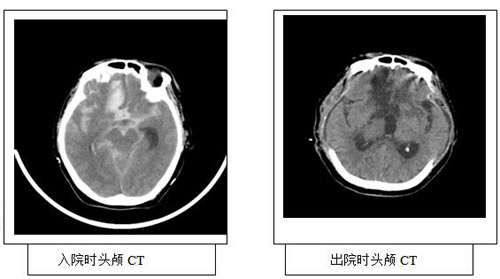

這是一位被多家醫(yī)院下病危通知書的特殊血液病患者,自入西安高新醫(yī)院血液科治療以來(lái)效果一直不錯(cuò),但于2016年5月31日突發(fā)意識(shí)喪失,在行頭顱CT檢查后發(fā)現(xiàn)其“蛛網(wǎng)膜下腔出血”即轉(zhuǎn)入神內(nèi)三科重癥監(jiān)護(hù)室緊急監(jiān)護(hù)治療。此時(shí)患者處于淺昏迷狀態(tài),雙側(cè)瞳孔直徑約2.5mm,光反射存在,雙眼向右凝視,左側(cè)肢體偏癱,左側(cè)病理征陽(yáng)性。Glasgow評(píng)分:E1V1M3=GCS5分。根據(jù)患者檢查結(jié)果,醫(yī)師給出的診斷是:蛛網(wǎng)膜下腔出血(Hunt分級(jí)Ⅳ級(jí))、癲癇持續(xù)狀態(tài)、全面強(qiáng)直陣攣發(fā)作、肺部感染、急性非淋巴細(xì)胞白血病M3型、高血壓病3級(jí)(很高危)。

術(shù)后患者持續(xù)高熱,嚴(yán)重腦水腫,采取亞低溫治療,降低腦代謝。尼莫地平持續(xù)泵入預(yù)防腦血管痙攣,同時(shí)發(fā)生嚴(yán)重高血鈉。由于患者為出血性腦血管病,在重癥ICU唐偉主任的幫助下開展了醫(yī)院首例枸櫞酸體外抗凝血液濾過(guò)治療,并且給予腰大池持續(xù)引流術(shù),減少蛛網(wǎng)膜下腔血量。加強(qiáng)護(hù)理,預(yù)防并發(fā)癥等,15天后患者逐漸脫離呼吸機(jī),病情逐漸好轉(zhuǎn),但肢體活動(dòng)功能尚未恢復(fù),后期經(jīng)高壓氧治療,患者已出現(xiàn)自主睜眼反應(yīng)和吞咽動(dòng)作,回當(dāng)?shù)蒯t(yī)院進(jìn)一步鞏固治療。